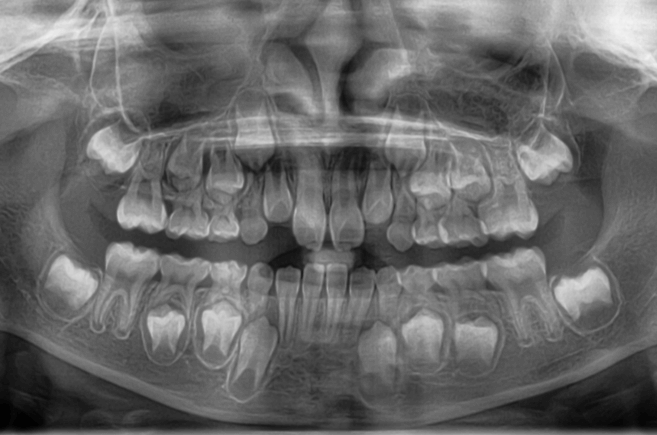

STEP2 精密検査

カウンセリング後、本格的に治療を進めるために精密検査に移ります。より詳しい口腔内の検査、顔・口内の写真撮影、レントゲンやCT撮影、歯型取りが具体的な内容です。顎の骨の歪みをはじめ、骨格的な問題が無いかも診察します。

診断結果 | 8歳7か月の男児 前歯の反対咬合(下顎前突)診断 |

治療内容 |

|

治療後の経過 | 動的治療は1年3か月で完了。反対咬合は改善されました。現在は3〜4か月ごとの定期検診で経過観察中で、今後本格的な矯正治療へ移行予定です。 |

治療期間 | 動的治療期間:1年3か月 治療回数:11回 |

治療費用 | 400,000円(税別) |